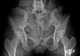

Spondyloepimetaphyseal dysplasia with joint laxity